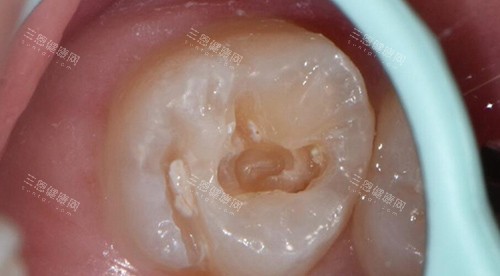

三、3D导航种牙,误差细过0.3mm

3D导板种植:用CT同口扫仪扫晒口腔数据,电脑规划好路线先做手术,误差控制喺0.3mm以内,唔使担心种歪。